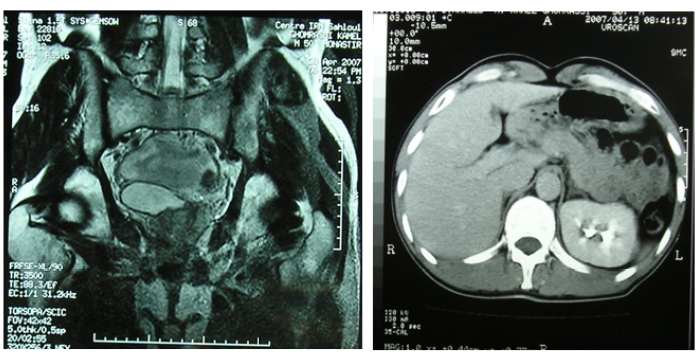

Seminal Vesicular Cyst: About 2 Case Report

Nizar Cherni, Abdallah Chaachou, Wael Ferjaoui*, Samir Ghozzi and Mohamed Dridi. 6(4): 85-87.